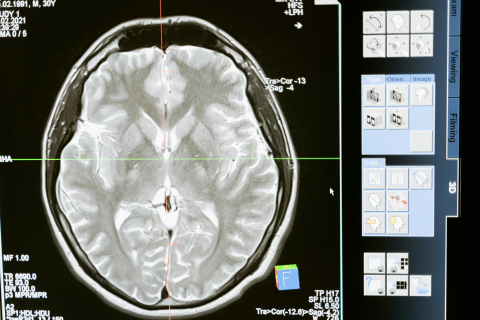

Un grupo de científicos descubrió cómo envejece nuestro cerebro. Spoiler: es por etapas.

Todo esto viene de un estudio hecho por la Universidad de Cambridge, dicho sea de paso.

En resumen, nuestro cerebro tiene cinco “épocas” bien marcadas: a los 9, 32, 66 y 83 años.

Veámoslas una a una:

Primera etapa (0-9 años): Durante la niñez, el cerebro se expande, se genera la materia gris (donde están las neuronas), la materia blanca (las conexiones entre ellas) y se forman todas las conexiones.

Segunda etapa (9-32 años): Es la “adolescencia cerebral”. Todas las conexiones neuronales se refinan, se vuelven más eficientes, se optimizan, y las diferentes zonas del cerebro se dividen y especializan.

Tercera etapa (32-66 años): Ahora sí, nos convertimos en adultos. No hay grandes cambios, más allá de que el cerebro se “estabiliza” y se lleva a la madurez cerebral.

Cuarta etapa (66-83 años): Esta etapa es el envejecimiento temprano y es cuando se nos empiezan a dañar las conexiones neuronales. Ahí es cuando comienza a fallarnos la memoria.

Y la quinta etapa (83+ años): en este momento el cerebro se nos reorganiza por completo. Las conexiones se debilitan y las diferentes zonas se vuelven más dependientes.

Entonces sí, resulta que nuestros cerebros tienen puntos de inflexión y por eso es que somos vulnerables en diferentes momentos de nuestras vidas.